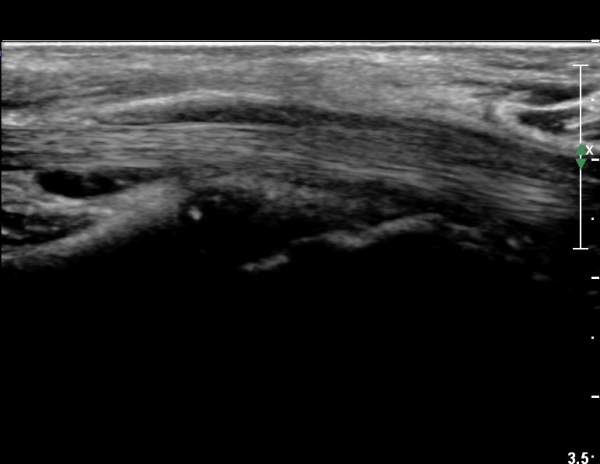

¼Õ¸ñ°ú ¼ö±Ù°ü±ÙÀ§ºÎ Ⱦ´Ü¸é°Ë»ç¿¡¼­  ÈûÁÙÀÇ ºñÈÄ¿Í ÈûÁÙ ÁÖÀ§ Ȱ¾×¸· ºñÈİ¡ °üÂûµÇ³ª

Á¤Áß½Å°æ ºÎÁ¾Àº °üÂûµÇÁö ¾Ê´Â´Ù(»çÁø 3, 4).